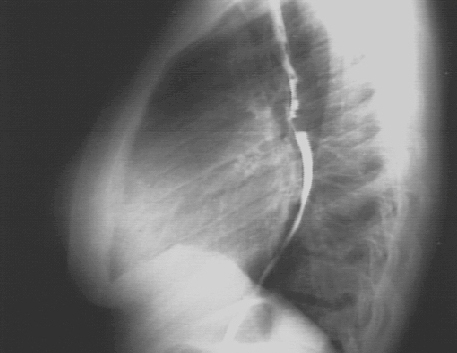

These chest X rays show left ventricular enlargement and left atrial enlargement. This PA view demonstrates the enlarged left ventricle as an increase in the inferolateral cardiac border associated with an increased cardiothoracic ratio. The markedly enlarged left atrium is manifested by the double contour within the heart border, an elevated left mainstem bronchus, and an enlarged left atrial appendage.

The lateral view with barium swallow, demonstrates posterior displacement of the esophagus by the markedly enlarged left atrium.